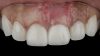

(9.) Postoperative photographs acquired after 2 weeks and 3 months of healing, respectively, demonstrating the reconstitution of an ideal tooth No. 9 marginal position in relation to its contralateral counterpart with increased soft-tissue thickness.

Figure 9

(10.) Postoperative photographs acquired after 2 weeks and 3 months of healing, respectively, demonstrating the reconstitution of an ideal tooth No. 9 marginal position in relation to its contralateral counterpart with increased soft-tissue thickness.

Figure 10

The patient in this case had undergone implant therapy at the site of tooth No. 9 and was restored with a cement-retained restoration more than 5 years prior. At presentation, the site demonstrated a peri-implant soft-tissue dehiscence that extended approximately 3-mm apical to the gingival margin of tooth No. 8. Thin and erythematous marginal tissue was evident at the zenith (Figure 2). The crown was removed, and a partial thickness flap was reflected using a papilla-sparing incision design. This revealed that the implant was positioned too far facially and that its body was visible through a very thin layer of bone (Figure 3 and Figure 4). The first objective of treatment was to minimize the facial extent of the emerging abutment and crown. To accomplish this, the facially positioned abutment and implant crown margin were both recontoured. The second treatment objective was to provide additional supracrestal soft tissue that would more adequately maintain the peri-implant margin. The tuberosity was selected as a donor site due to its dense, high-quality connective tissue, low propensity for shrinkage, and association with minimal patient discomfort. Once the graft was secured (Figure 5 through Figure 7), the flap was coronally positioned (Figure 8). After a healing period of 2 weeks, the margin of tooth No. 9 exhibited an ideal position in relation to its contralateral counterpart and demonstrated increased soft tissue thickness (Figure 9). Three months postoperatively, further healing had improved the esthetics and the position of the margin had been maintained (Figure 10).